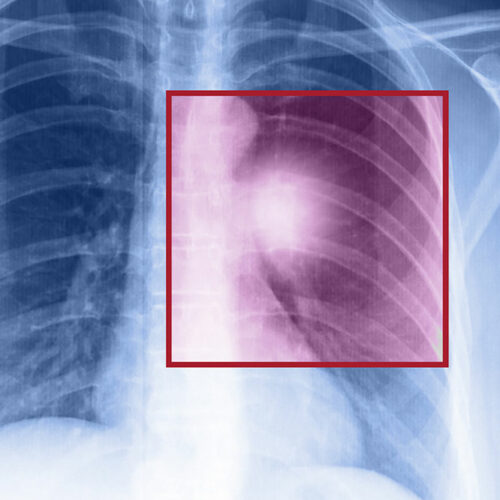

Lung cancer – Types, symptoms, and causes

When the cells in the lungs begin to abnormally multiply and grow, it results in cancer. Lung cancer is one of the leading causes of death in the world. And the risk of suffering from this life-threatening disease is even higher when one is a smoker. Herein, we discuss the various factors that come into play when it comes to lung cancer.